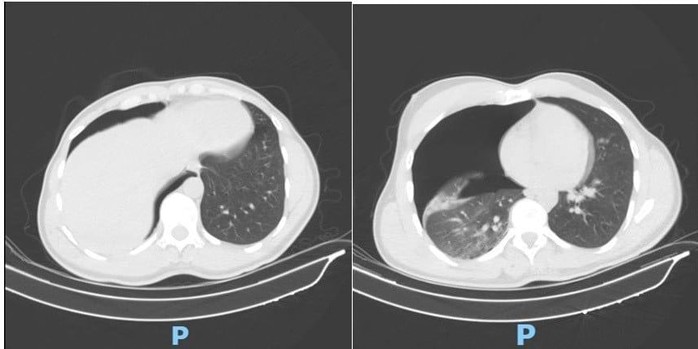

Phim CT scan lồng ngực sáng ngày nhập viện ghi nhận tràn khí màng phổi phải lượng nhiều

Ngay khi tiếp nhận, các bác sĩ đã khẩn trương thực hiện CT scan lồng ngực, mạch máu khẩn cấp. Kết quả cho thấy người bệnh bị tràn khí màng phổi phải lượng nhiều gây chèn ép phổi, gãy cung bên xương sườn 2, 3, 4 phải và gãy phức tạp 1/3 giữa xương đòn phải, di lệch nhiều kèm mảnh rời.

Trước nguy cơ suy hô hấp nặng, ê-kíp Khoa Phẫu thuật Tim – Lồng ngực – Mạch máu đã tiến hành đặt dẫn lưu màng phổi phải cấp cứu. Ca thủ thuật do TS-BS Đồng Đức Hưng trực tiếp thực hiện. Nhờ xử trí nhanh chóng, chính xác, phổi phải nở lại tốt, tình trạng hô hấp của người bệnh cải thiện rõ rệt chỉ sau vài giờ.